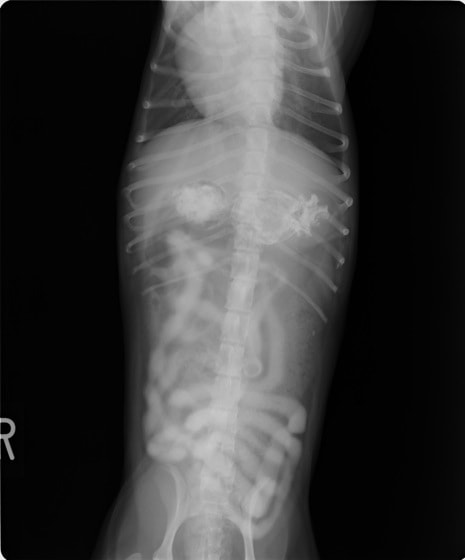

4歳 アメリカンショートヘアー

主訴:3日前から嘔吐が続き、食欲も落ちてきたのこと。

対症療法(症状に対する治療)に反応しないため、精査を実施。

一般血液検査:問題なし

単純レントゲン検査:胃内ガス陰影・腸内ガスが少量認められる。

嘔吐が改善しないため、消化管バリウム造影検査を実施。

以下、

消化管バリウム造影レントゲン

バリウム造影3時間経過するも、胃内からバリウム排泄なく同日内視鏡検査を実施。

内視鏡検査結果:内視鏡下にて、バスケット鉗子を用いて摘出。

症例は、机の上に置いていたピスタチオのお菓子を誤飲していました。その後の経過は良好です。本症例は、内視鏡下にて摘出ができましたが、球状・立体などの大きな異物は、腸の途中で詰まりやすく、内視鏡下での摘出が困難な場合もあります。その際は、開腹下にて腸内の異物を摘出しなくてはなりません。動物たちは、思わぬ物を誤飲することがあります。お留守番時・就寝時は、誤飲をしやすい時間帯ですので注意しましょう。

◎バリウム造影検査とは??

ヒトと同様に特殊な液体を飲み、消化管内のバリウムの流れを経時的に撮影していきます。

胃の粘膜状態、胃から腸への通過障害の有無などを確認することが出来ます。また、単純レントゲンでは写することのできない物もバリウムを飲む事で写し出されることが多くあります。検査をするためには、前日の夜からの絶食が必要になりますが麻酔などは必要ありません。